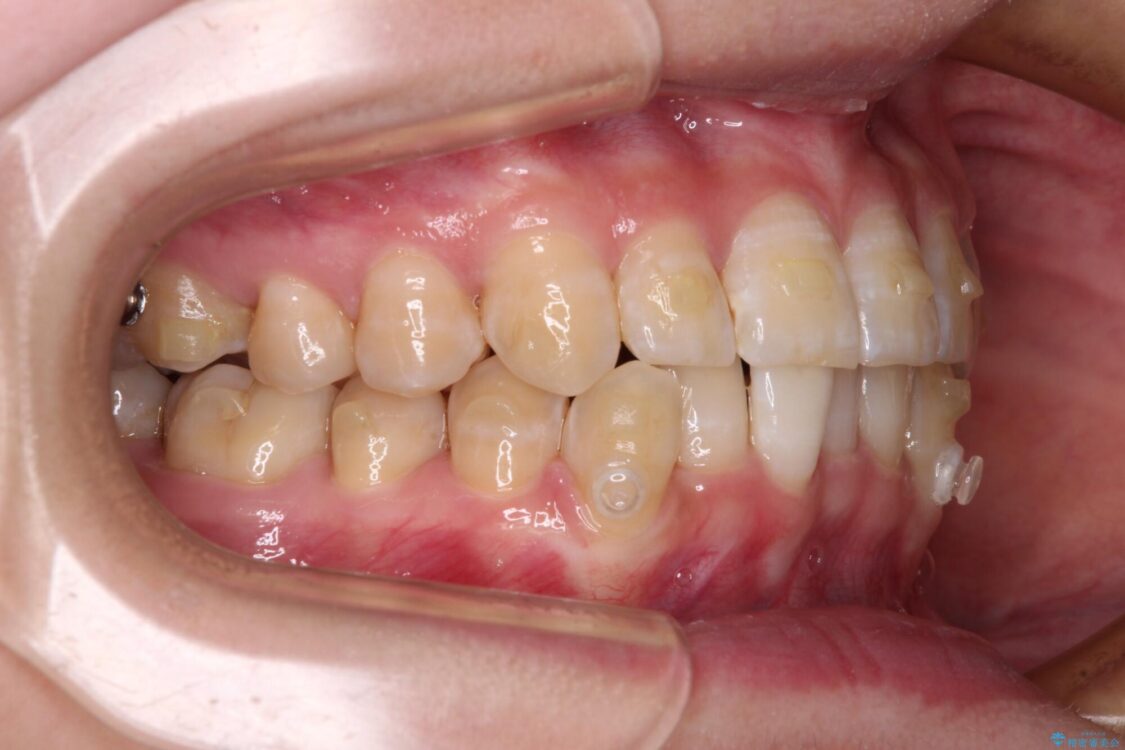

下顎の八重歯を気にして来院された患者様です。

下顎前歯にデコボコが集中していたため、顎間ゴムによる後方移動とIPR(歯と歯の間を削ること)により歯列を整えることとしました。

治療前、下顎前歯のデコボコが集中しており、奥歯の咬み合わせは、上顎に対して下顎が前方位にある状態でした。下顎の歯列を後方へ移動させる治療はインビザラインの得意とするところですので、1年程度で無事に治療を終えることができました。

治療途中

• 【モニター】下顎前歯のデコボコをインビザラインできれいに 治療途中画像